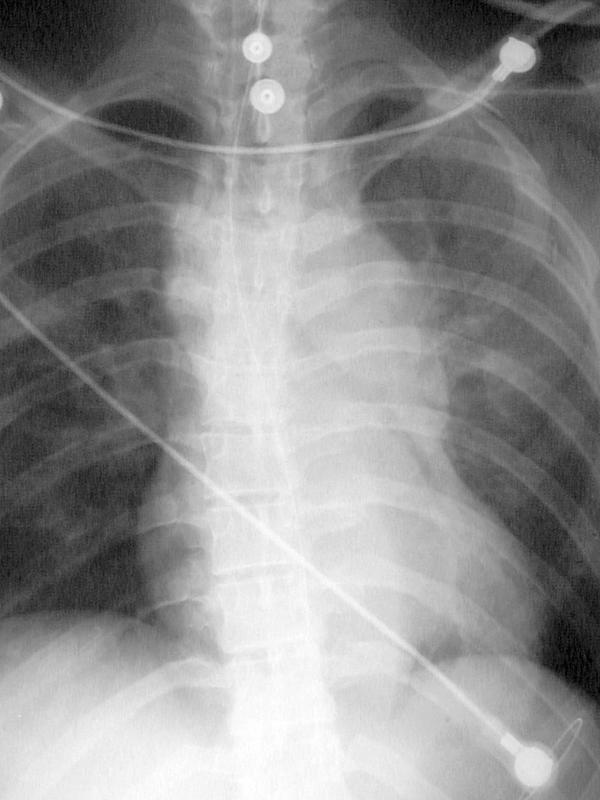

Gallery Blunt Chest Trauma Tr Aortic Injury Case 1a

Case 1a